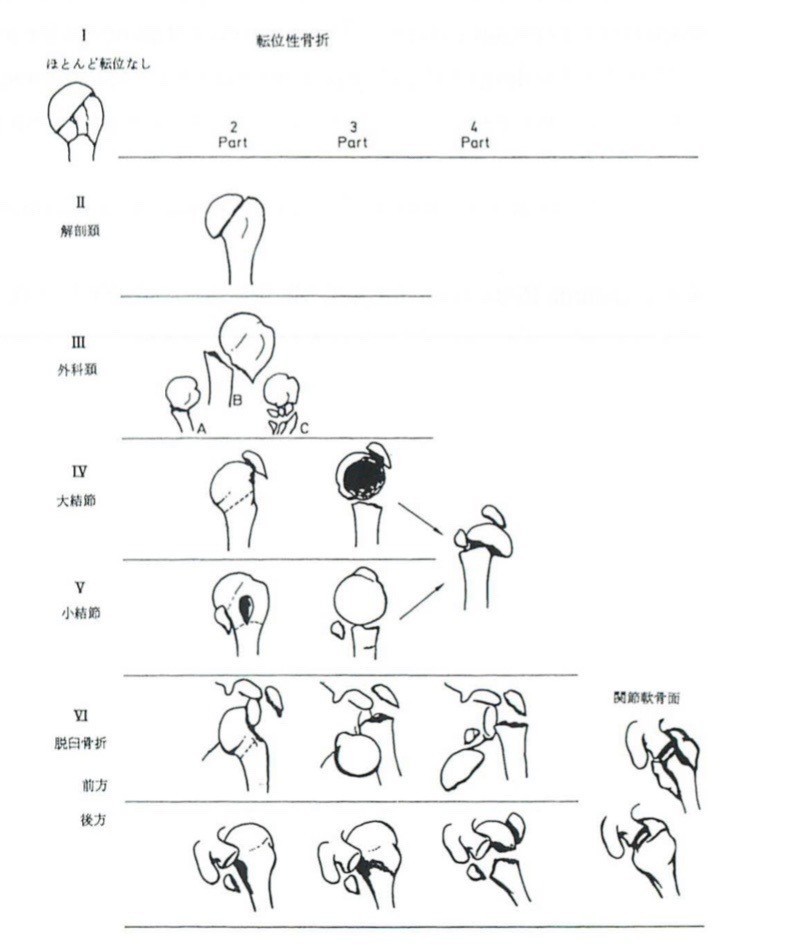

上腕骨近位端骨折におけるneer分類 たくみロドリゲス 運動器理学療法士 Note

上腕骨近位端骨折 一般社団法人 日本骨折治療学会 骨折の解説

上腕骨近位端骨折 一般社団法人 日本骨折治療学会 骨折の解説

上腕骨近位端骨折について こんな時は救急外来へ 症例別q A 社会医療法人 有隣会 東大阪病院 大阪市 城東区

上腕骨近位端骨折のリハビリ 骨癒合を進めるために必要な4つの要素 リハ塾 理学療法士が教える心と身体のブログ

上腕骨近位端骨折のリハビリ 骨癒合を進めるために必要な4つの要素 リハ塾 理学療法士が教える心と身体のブログ